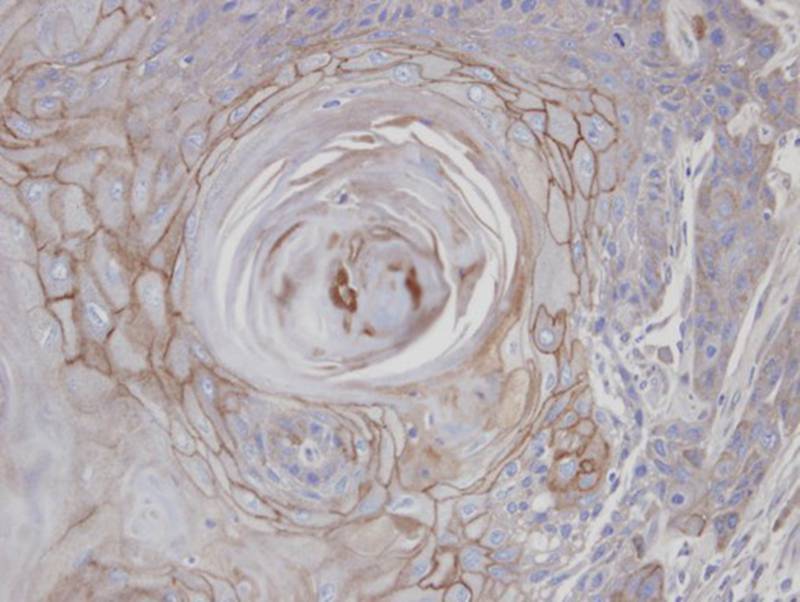

Immunohistochemical analysis of paraffin-embedded SCC25 xenograft, using MAN1B1 antibody at 1: 100 dilution.